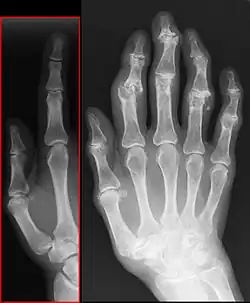

Radiologie

à gauche articulation sans arthrose

La radiographie standard, sans préparation, est suffisante au diagnostic de la maladie arthrosique.

Quatre signes radiologiques sont caractéristiques :

- le pincement de l'articulation par destruction du cartilage (diminution de l'épaisseur du cartilage) ;

- une condensation osseuse sous le cartilage ;

- la présence d'excroissances osseuses ou ostéophytes ;

- la présence de géodes (trous à l'emporte-pièce) dans l'os autour de l'articulation.

Il n'y a pas de parallélisme entre l'importance des signes radiographiques et les symptômes ressentis : une arthrose importante sur la radiographie peut rester asymptomatique. Inversement, une arthrose très douloureuse peut ne présenter que de modestes altérations radiologiques.